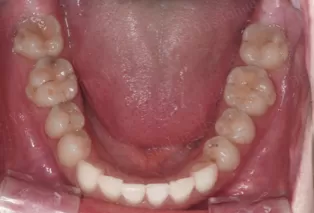

Photos intra-orales